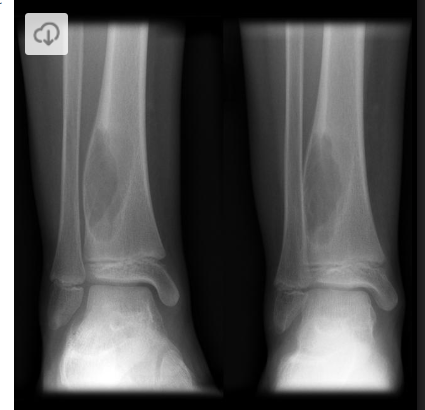

Cisto ósseo aneurismático

Acomete paciente jovem (fise aberta);

Localização excêntrica, aspecto em favo de mel no RX;

Pode ter reforço periosteal;

RM:lesão multicística; Septos + nível liquido-liquido (lesões dx diferencial: COS fraturado, COA, TCG ou osteossarcoma telangiectásico).

Primário ou Secundário à outros tumores: TCG, DF, Condroblastoma.